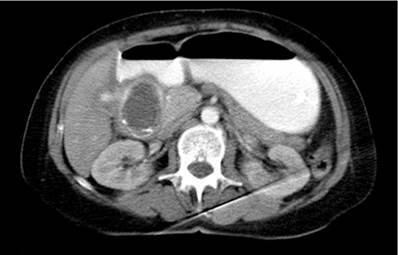

En TACab se evidencia obstrucción intestinal por imagen intraluminal a nivel de la primera porción duodenal de 4,5 x 3 cm (Figura 1 y 2) asociado con neumobilia y presencia de paso del medio de contraste a la vía biliar, lo que cumple los criterios de la triada de Rigler, adicionalmente dilatación de la cámara gástrica secundaria a obstrucción de la luz duodenal y una EVDA con presencia de cálculo impactado en el bulbo duodenal (Figura 3 y 4).

Figura 1 Tomografía axial computarizada de abdomen que evidencia la presencia de imagen redondeada que obstruye la luz duodenal.